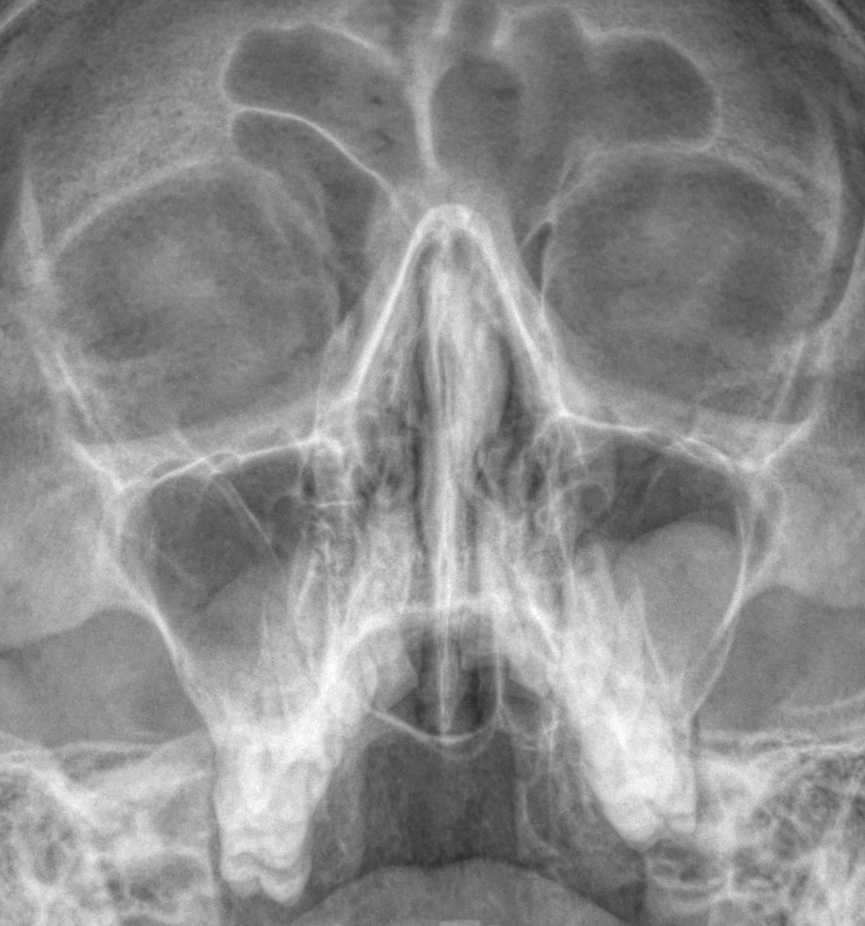

Этот вопрос ставит в тупик не только пациентов, но и бывалых терапевтов, гастроэнтерологов, лор-врачей и многих...